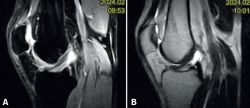

No se evidenciaron alteraciones significativas en el estudio radiológico simple realizado. En la RM se evidenció la presencia de un ganglión del LCA con afectación de su fascículo posterolateral (Figura 1).

Figura 1. Imagen de resonancia magnética del quiste sinovial localizado en el ligamento cruzado anterior. A: secuencia PDW SPIR en corte sagital de la rodilla; B: secuencia PDW SPIR en corte coronal de la rodilla.